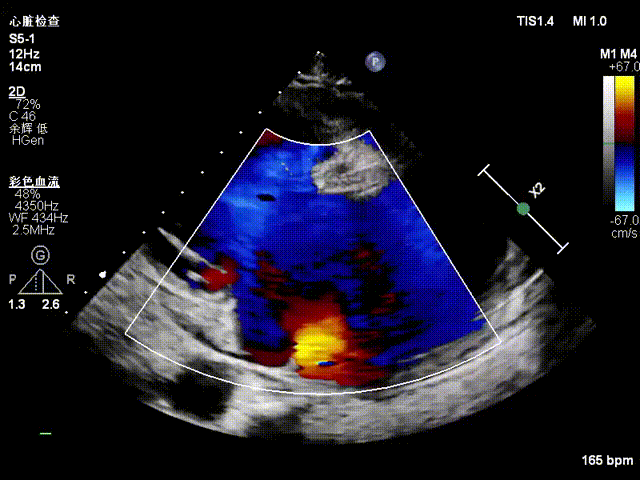

One 14T K-Clip® was implanted at the junction of the posterior and septal annuli of the patient's tricuspid valve, and one 16T K-Clip® was implanted at the junction of the posterior and anterior annuli. The overall annular area was reduced by 45%. Leaflet coaptation was improved, and regurgitation was effectively reduced from severe preoperative to moderate. The overall surgical outcome exceeded expectations, and the procedure was successfully completed.

Postoperative regurgitation